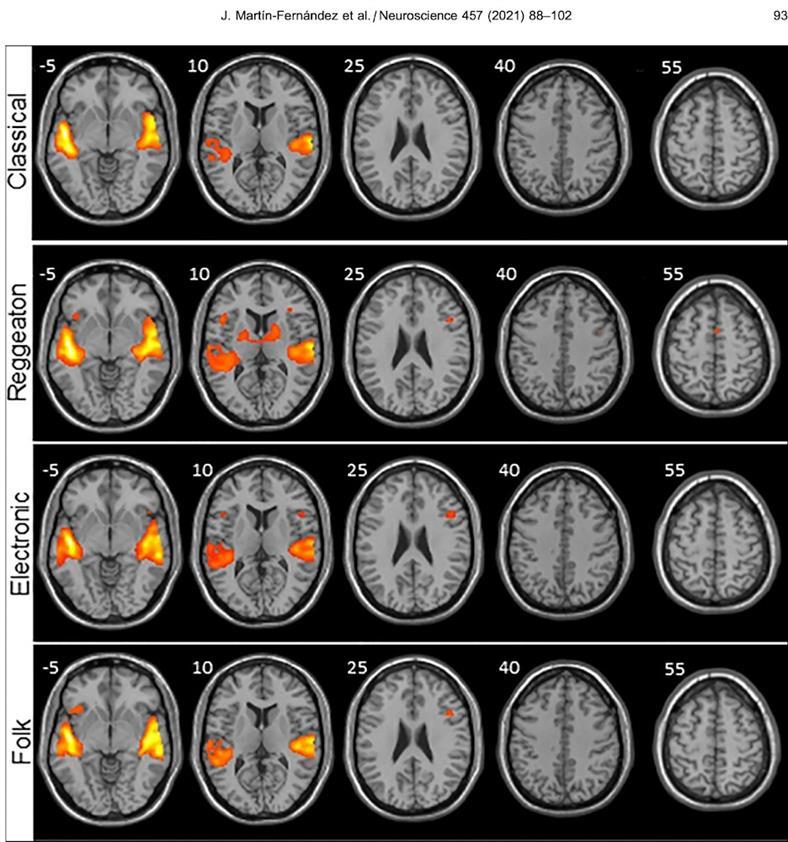

Según el estudio neurológico, el género proveniente de centroamérica provoca una mayor activación en las regiones del cerebro encargadas de procesar no sólo los sonidos, sino también el movimiento. Para llegar a esta conclusión, estudiaron la actividad cerebral que produce escuchar diferentes géneros musicales.

Los investigadores estaban atentos a las señales de activación en los distintos hemisferios del cerebro, siendo el reggaeton el que mostró mayor actividad en los lugares encargados de procesar los sonidos y movimientos. En otras palabras, despertó una zona “primitiva” del cerebro relacionada con los ganglios basales -encargados de modular la postura, comenzar un movimiento, y están involucradas en el sistema del placer-.

“Hay más regiones cerebrales auditivas y motoras que se activan y por lo tanto hay una mayor maquinaria trabajando en procesar la música”, señaló el sitio.